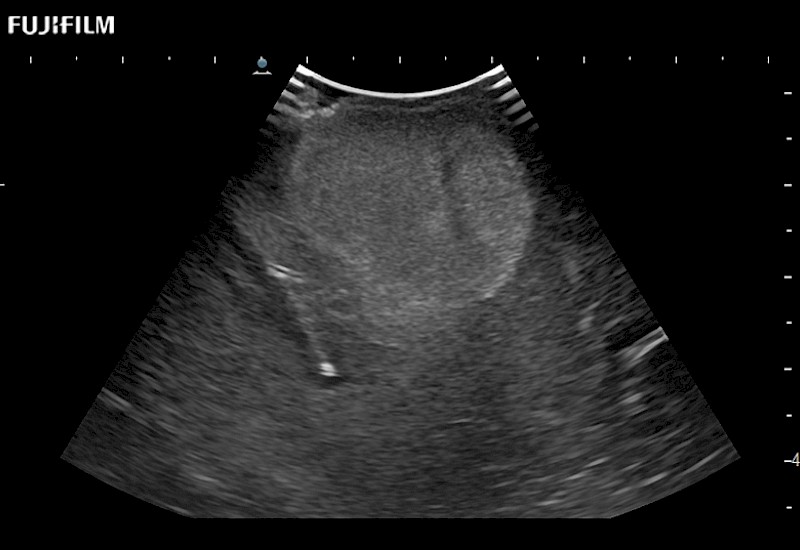

Fujifilm Healthcare understands that neurosurgeons demand excellence in their operating rooms — from their staff and the equipment they depend on. Fujifilm Healthcare's dedication to neurosurgery provides outstanding ultrasound technology, professional support, and the specialized tools necessary to best perform comprehensive real-time ultrasound imaging.

Dedicated Intraoperative Ultrasound

Solutions for Neurosurgeons

For precise neurosurgery ultrasound imaging, Fujifilm Healthcare offers premium level solutions that include:

Extraordinary high-resolution digital imaging

Exceptional transducers

for use during: Cranial guidance, Burr-Hole guidance, Spinal Cord guidance, Pituitary guidance, Micro-Surgery guidance

Our dedication to neurosurgery allows us to offer superior image quality, outstanding system reliability and intuitive use of cutting edge technology.